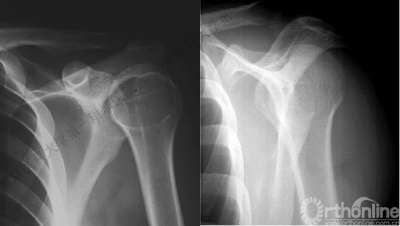

病例2

男性,48岁,坠落伤致左肩关节肿痛、活动受限1天。

病例3

男性,27岁,车祸致右肩部肿痛、活动受限6小时。

术后肩关节X线片

VS

Ⅱ型: +肱骨颈骨折+小结节骨折(病例3)。

Ⅲ型: +肱骨颈骨折+小结节骨折+大结节骨折(病例2),以骨折线向肱骨近端外侧壁延伸为另一特征。